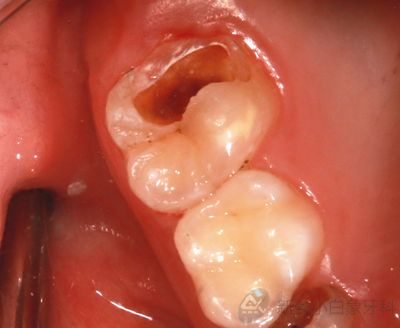

治疗计划:16护充

治疗:16去腐质,备洞,隔湿干燥,Daycal垫底,纳米充填及行纳米封闭术,调合。

2.png

治疗中